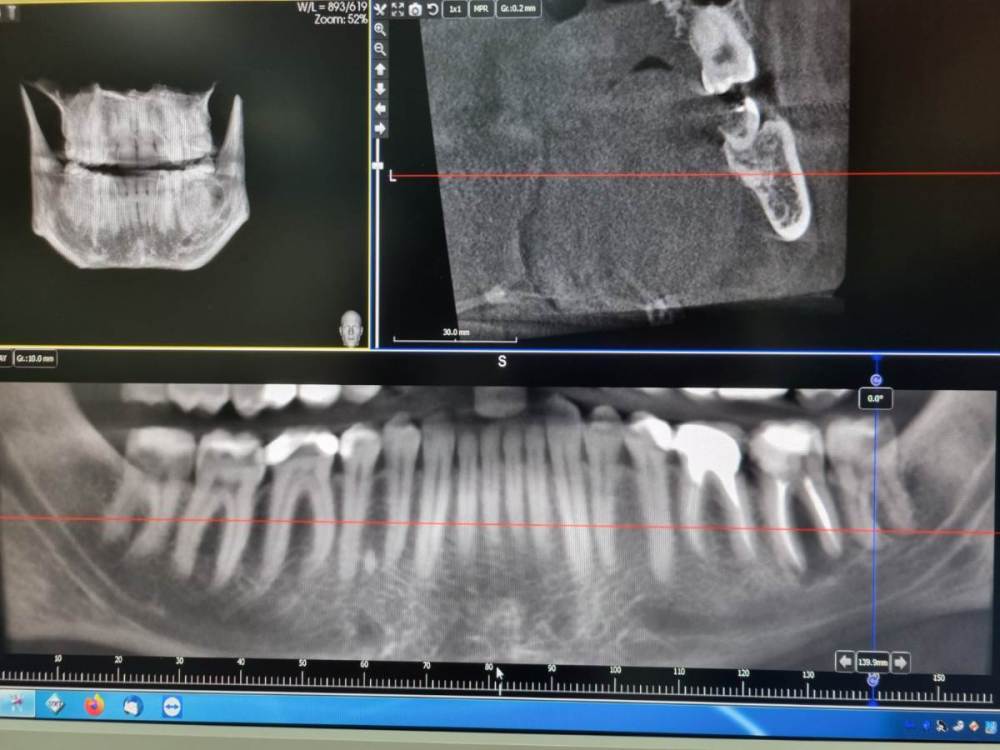

IvanK Опубликовано 20 апреля, 2023 Поделиться Опубликовано 20 апреля, 2023 20 часов назад, Chelovek2012 сказал: А это касается и других зубов, у которых есть только стенки? Нету технологии спасти зуб (во своих стенках) без коронки? покажите панорамный снимок (ОПТГ), тогда смогу сказать о других зубах судя по рг снимку есть все шансы получит кариес корня 5го зуба, что приведет к удалению зуба по поводу технологии спасения зубов - это только профилактика стоматологических заболеваний, а именно самостоятельная и профессиональная гигиена полости рта, своевременные осмотры и диагностические мероприятия у врача-стоматолога 1 Ссылка на комментарий

IvanK Опубликовано 21 апреля, 2023 Поделиться Опубликовано 21 апреля, 2023 Здравствуйте, год - это уже срок, не очень актуально, но, исходя из этого снимка, я бы рекомендовал: проверить контактный пункт 15-16, состояние пломб 11,12, на 25 возможно кариес под коронкой 15, 26, 37 оценить по дкт корни, далее протезирование 36 кариес под коронкой оценка контактных пунктов 45-46-47 1 Ссылка на комментарий